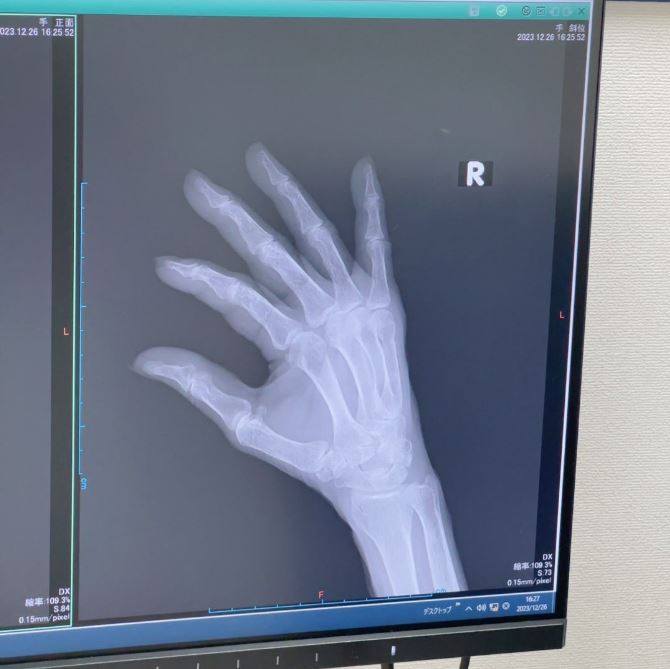

ブログには、整形外科を受診したときのことが記されていて、「昨日受診した○○整形外科の院長先生の治療には感動しました‼️」と書き出し「小指 第3関節の下 綺麗に折れてるのが 分かりますよね」「折れた骨が 内側に入り込んでるのが分かります」と骨折した指のレントゲン写真とともに説明。